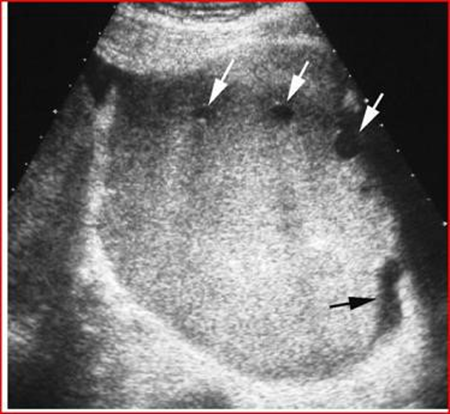

The ultrasonographic study shows two large masses, one in the left pelvic portion and the other in the right pelvic portion.

The masses appear homogeneous and slightly echogenic with small cystic areas around the periphery. There is a small amount of free fluid in the pelvis (Figure 3).

Figure 3: Transverse ultrasound shows a well-defined, homogeneous and hyperechoic mass, with focal cysts at the periphery (white arrows) and a small amount of free fluid (black arrow).